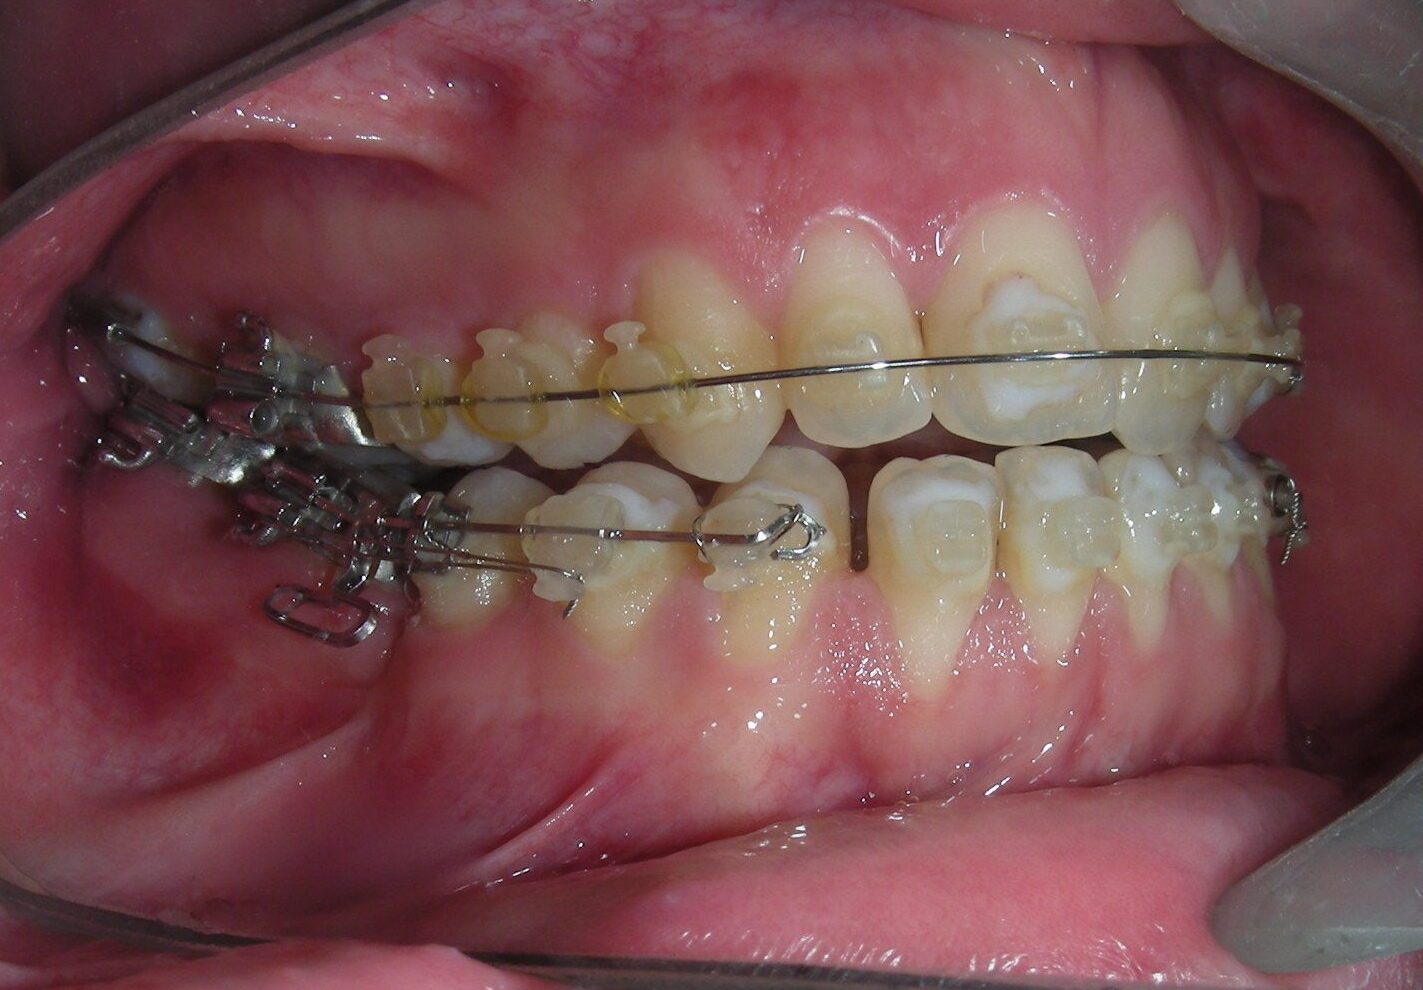

Having successfully achieved the expansion, we proceed to the intrusion of the posterior superior sectors, modifying the Hyrax by adding anchoring hooks at the buccal level of the first premolars. Using the Hyrax as anchorage, we sought a parallel intrusion. This could be replaced by a palatal bar. TADs were installed bilaterally at the mesial level of the first molars, inserting them as parallel as possible to the roots.

Simultaneously we begin with the alignment of the lower arch ,Simultaneously we began with the alignment of the lower arch with Roth prescription ceramic braces .022 . Henry Schein®

As the reader may infer, alignment and leveling of the upper anterior segment are being intentionally deferred at this stage of treatment. This strategic decision is based on the primary objective of closing the anterior open bite not through anterior extrusion, but by means of controlled posterior intrusion. This biomechanical approach promotes a counterclockwise rotation of the mandible, which leads to a increase in the facial axis angle and improvement in vertical facial proportions. By avoiding early anterior alignment, we prevent any premature vertical displacement of the upper incisors.

Clinical changes became evident after 12 months of treatment with posterior intrusion with TADs and nickel-titanium closed coil spring (NiTi), until subsequent follow-up appointments revealed no further significant changes. At that point, it was noted that the most distal molars remained in occlusal contact and had not followed the intrusive movement of their mesial neighbors.